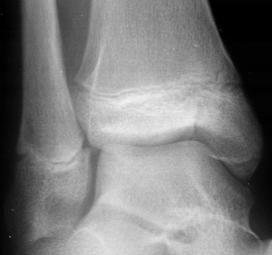

Rinichiul drept Rinichiul

drept

Extravazarea substantei de contrast Defect de

umplere - pol superior

Rinichiul stang

Sistem

caliceal, ureter, vezica urinara ocupate de un cheag de sange